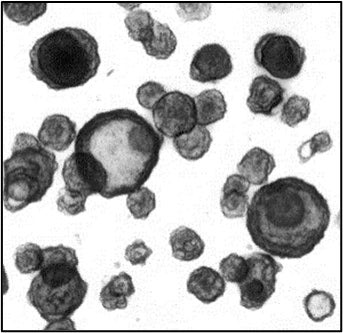

図1.細胞老化誘導した小腸オルガノイド

単層培養した小腸オルガノイドにシスプラチンを5日間処理することで、細胞老化の検出方法であるSA β-gal染色により染色される細胞の数が増加したことを確認しました(図1)。また、遺伝子発現量を評価したところ、シスプラチンの処理により細胞老化や炎症に関する遺伝子の発現量が増加したことを確認しました(図2)。

図1.シスプラチンによるSA β-gal染色陽性細胞の増加